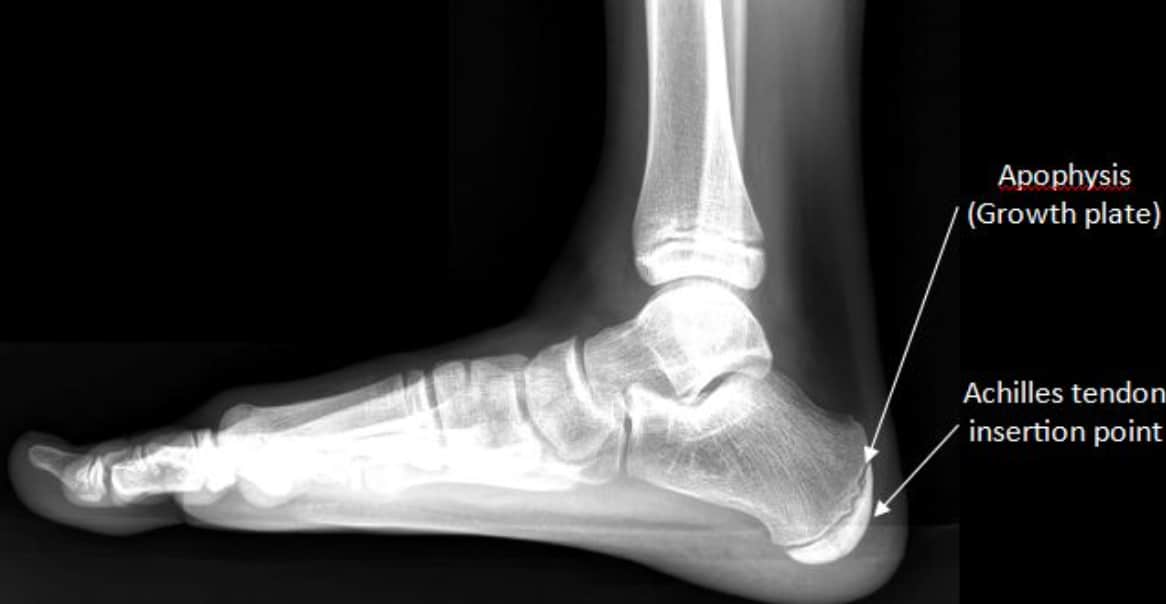

Diagram of a child's foot highlighting Sever’s Disease inflammation at the heel growth plate and Achilles tendon tension.

s heel pain sidelining your young athlete? Sever’s Disease is a common growth plate condition that causes sharp pain during sports and growth spurts. At Vertical Chiropractic of Sarasota, we provide specialized pediatric extremity care to address the root cause of heel inflammation, helping your child move comfortably and get back in the game without the “wait and see” approach.